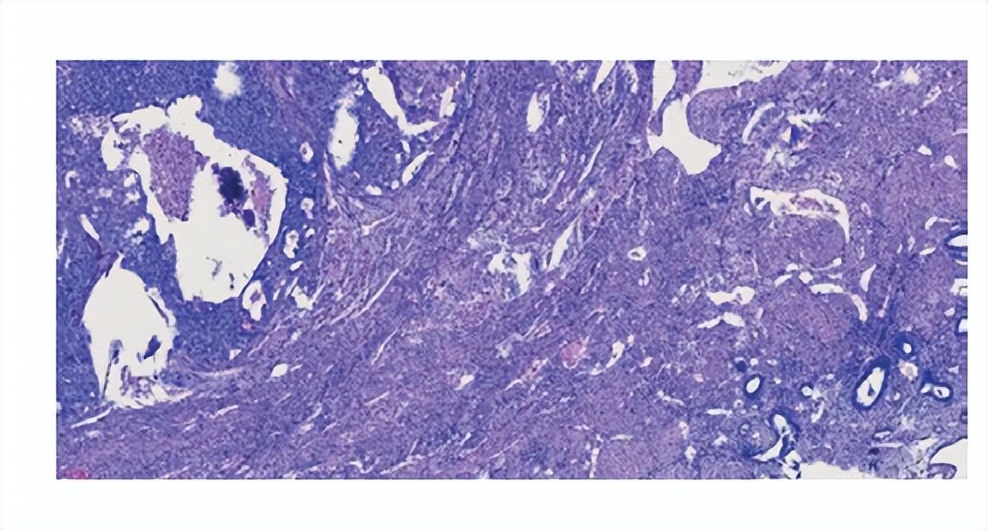

后续我们再进行开腹手术后,发现她的右卵巢囊实性肿物直径12 cm,与周围肠管、子.宫后壁紧密粘连,子.宫如怀孕12周大小,剖开子.宫显示宫腔内膜光滑,肌层内腺肌瘤结节切面呈鱼肉状,再将其切片送去快速病理检查发现右卵巢分化差的恶性肿瘤,考虑为腺癌。